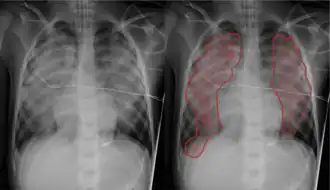

Pulmonary edema with small pleural effusions on both sides | |

Chest X-ray has been used for many years to diagnose pulmonary edema due to its wide availability and relatively cheap cost.[4] A chest X-ray will show fluid in the alveolar walls, Kerley B lines, increased vascular shadowing in a classical batwing peri-hilum pattern, upper lobe diversion (biased blood flow to the superior parts instead of inferior parts of the lung), and possibly pleural effusions. In contrast, patchy alveolar infiltrates are more typically associated with noncardiogenic edema.[3]